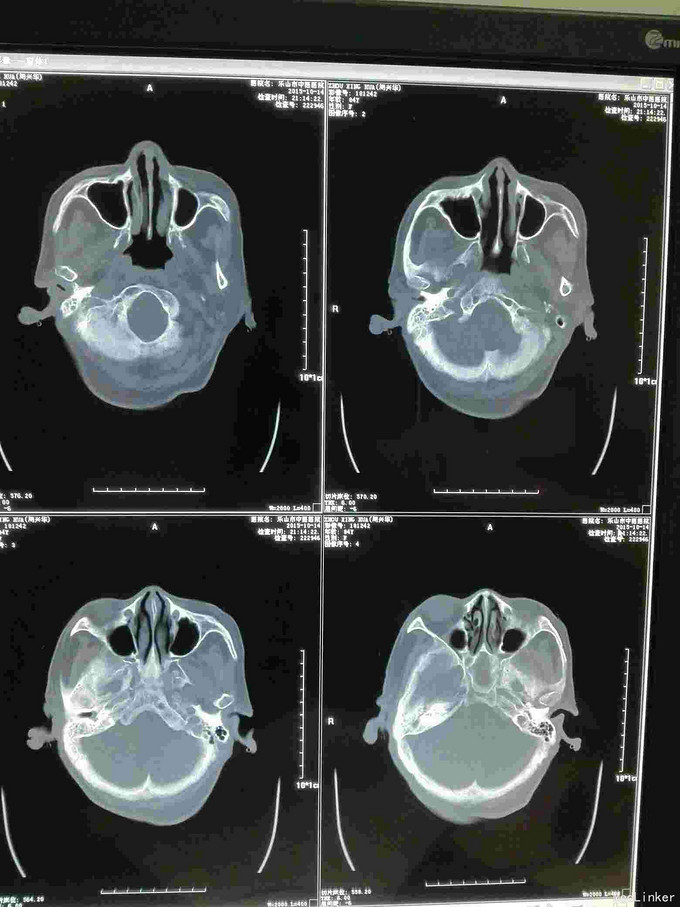

急诊CT病例

主诉 病史

昏迷不醒就诊